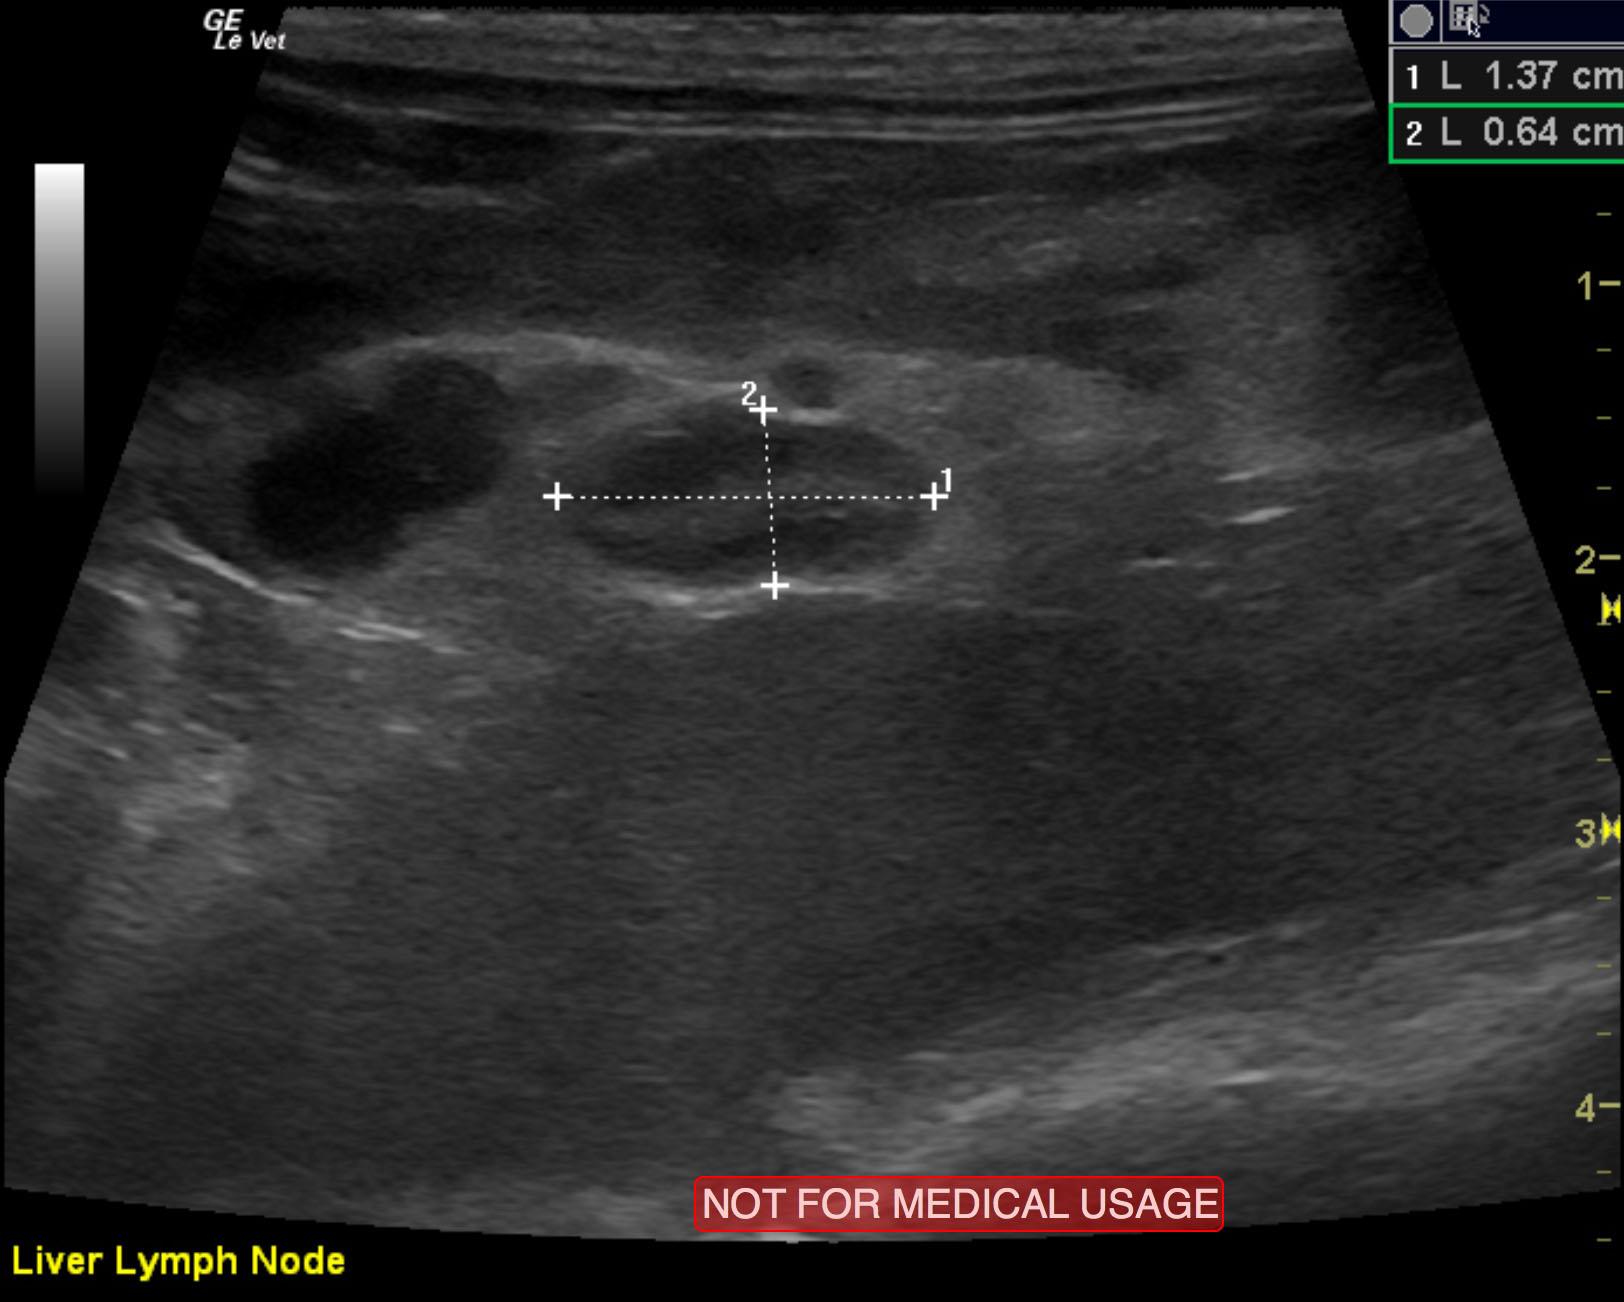

The left adrenal gland comprised a mass that measured 2.2 x 1.12 cm. Capsular expansion was noted at the caudal pole with pericapsular inflammatory pattern. It appeared significantly vascular with a trace amount of free fluid noted adjacent to it. This suggests a fairly aggressive process, but there was no evidence of vascular invasion noted. The right adrenal gland was uniform and measured 0.72 x 0.32 cm. Lymph node enlargement was noted in the epigastric region and measured 1.02 x 0.82 cm. A separate lymph node medial to the spleen was also enlarged, measuring 1 x 0.82 cm.

elvis_jones_ferret_adrenal_neoplasia_2elvis_jones_ferret_adrenal_neoplasia_right_adrenal_normalelvis_jones_ferret_adrenal_neoplasia_hepatic_ln